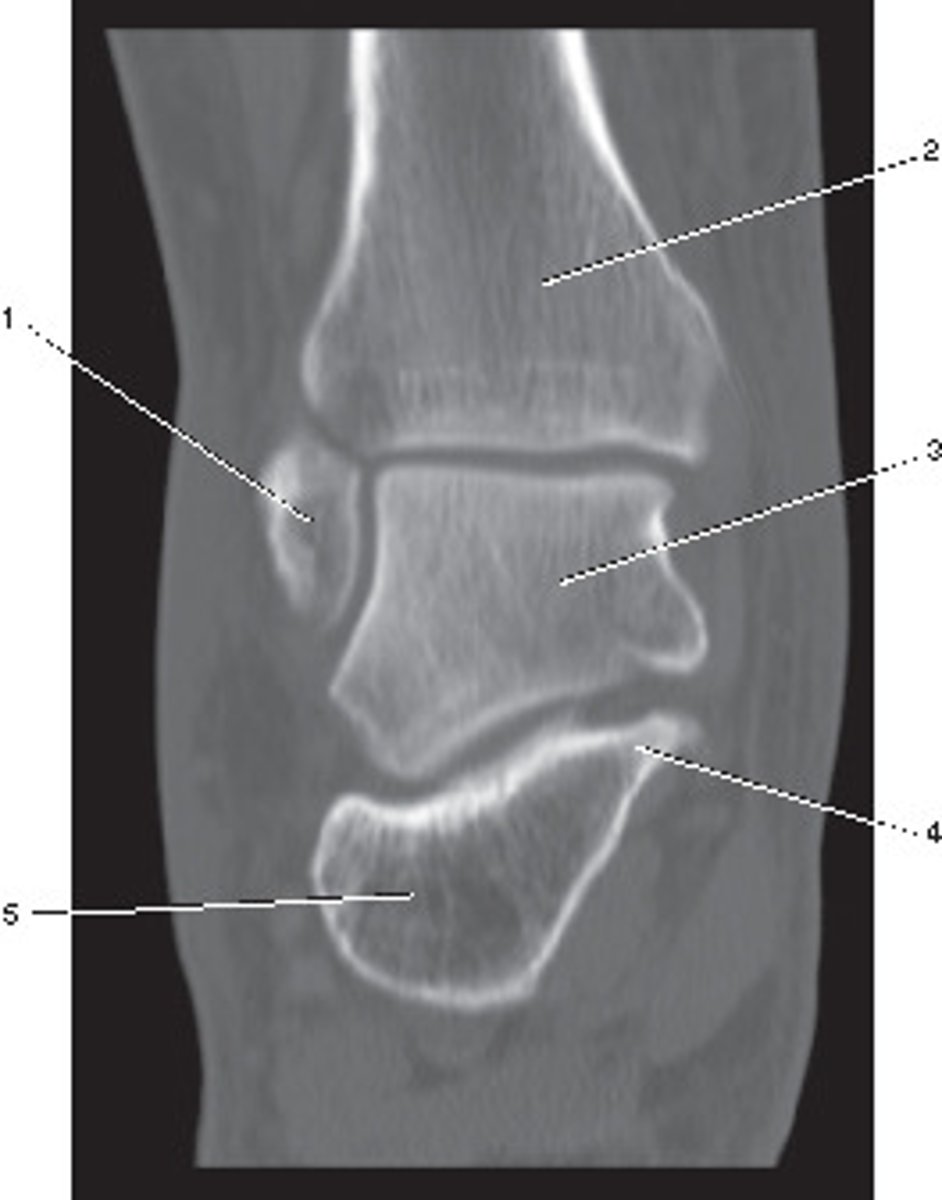

Fibula

Number 1 corresponds to which of the following?

<p>Number 1 corresponds to which of the following?</p>

Talus

Number 2 corresponds to which of the following?

<p>Number 2 corresponds to which of the following?</p>

Sagittal

What anatomic plane best describes this image

<p>What anatomic plane best describes this image</p>